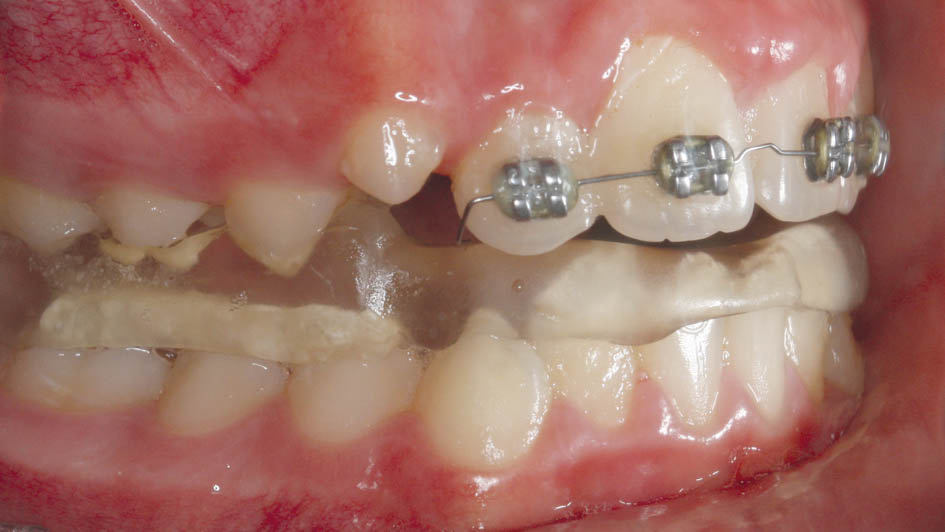

شکل 73-5: نمای روبروی بیمار

شکل 75-5: نمای روبروی بیمار

بعد از پروترودشدن قدامیها حالا میتوانید یک پلاک آندرسن (شکل 76-5 و 77-5) بسازید. میتوانید برای پلاک آرک لبیال نگذارید. در این مواقع مصرف پلاک تداخلی با داشتن براکتهای قدامی بالا ندارد و همزمان با مصرف این پلاک میتوانید سیم قدامیهای بالا را هم ضخیم کنید تا همزمان با رشد مندیبل، دندانهای بیمار هم مرتب شود.